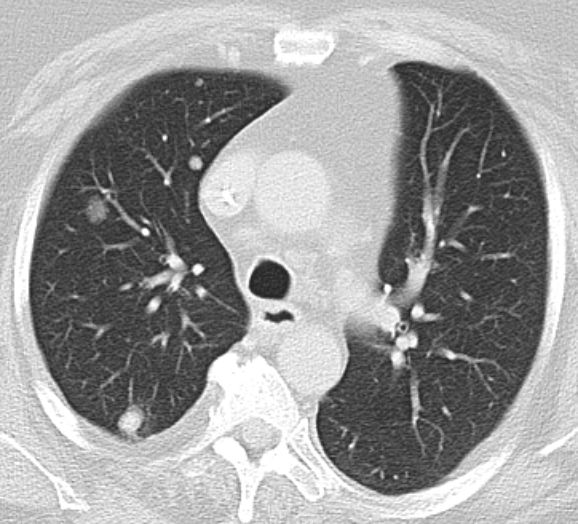

| Lunge | 58-jährige Frau, die vor 3,5 Jahren ein

Endometriumkarzinom pT2 pNo(0/33) Mo G1 hatte. 10 Monate später Pleuraerguss,

pulmonale Metastasen. Jetzt 3. Progress Carboplatin, Taxol, MPA.![]() |